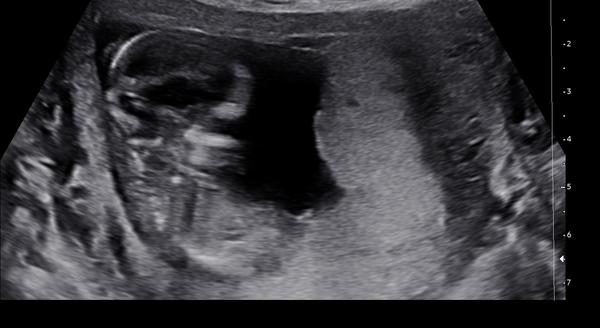

Dokáže lékař odhadnout pohlaví v 13. týdnu?

Ahoj všichni! Doktor mi dnes ve 13. týdnu řekl, že odhaduje kluka. Hodně jsem četla, že v brzkých týdnech je to celkem nerozeznatelné. Dokáže někdo třeba porovnat se svým ultrazvukem? Popř. Trefil se doktor vám?

@babymama6699 rekl, ze odhaduje, ne ze 100 procent kluk, takze modrou vybavu bych jeste nekupovala. Co kdyby se tady holky - absolutni laikove schodli na tom, ze pohlavni hrbolek je holka, jak byste potom pristupovala ke svemu lekari? Asi to musi byt mazec byt tehotna a verit vic lidem na modrym koniku nez doktorum. Ve 13 tt je dulezita nosni kustka a sijove projasneni samozrejme mimo jine a to je urcite v poradku, kdyby ne tak pohlavi nikdo neresi. Drzim palce at i zbytek tehotenstvi je zdrave, krasny zazitek z porodu a at na svet vykoukne milovany zdravi miminko 🍀